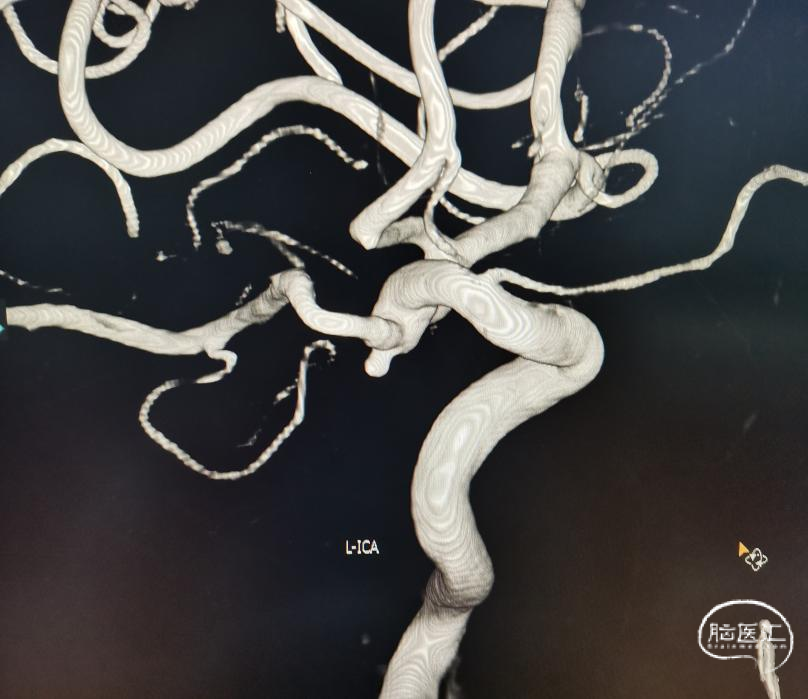

怀疑:左侧后交通的动脉瘤。又上一张CTA。

简单看看,还行。患者辗转到位,还是先安排一下造影吧。于是直接造影。原来跟我们评估的差不多,还是左侧后交通动脉瘤。